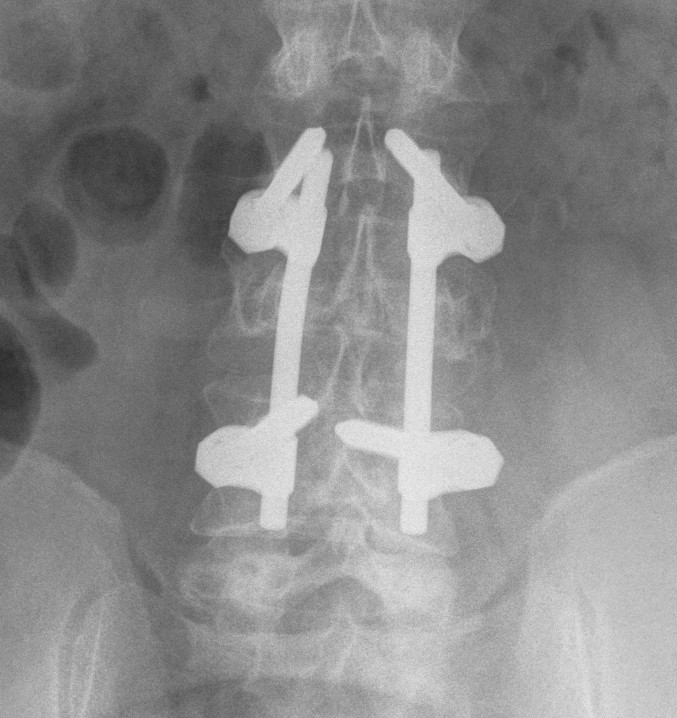

2. Burst Fracture

X-ray

- pedicle widening on AP

Posterior instrumentation

Technique

- ligamentotaxis clears canal / PLL acts as bowstring

- pedicle screws lumbar, avoided in thoracic

- use transverse process and pedicle hooks in thoracic

- bone graft inserted via pedicles

- need to do before 5 days post injury